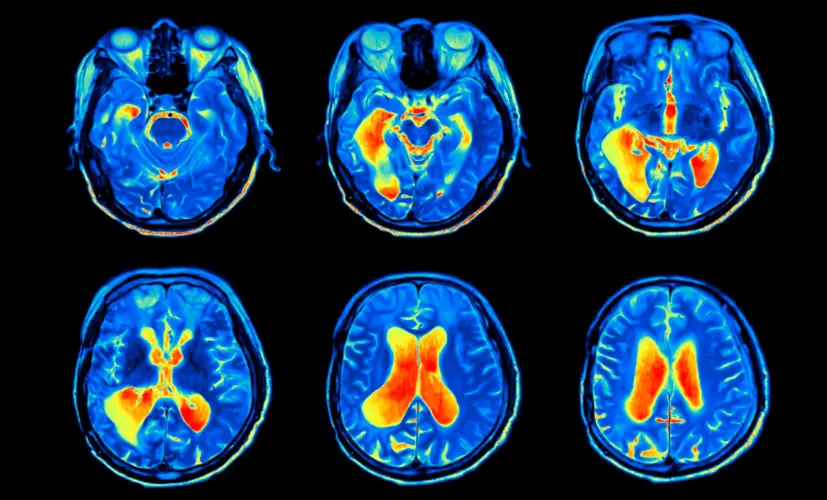

What's the connection between brain vessels, heart disease, and cognitive function?

– Why do people with cognitive decline often also suffer from heart disease and clogged brain vessels?

– The blood vessels throughout the body are closely connected. If the vessels in the brain are clogged with plaque, they receive fewer nutrients. That's where cognitive decline and other serious issues begin.

The same goes for the heart. People with cognitive decline are 59% more likely to develop coronary artery disease or atherosclerosis, and 34% more likely to suffer a stroke. As we've discussed, cognitive decline can also lead to depression, which further increases the risk of cardiovascular disease. Add in the overuse of Aricept, which negatively impacts brain function-and suddenly, the person suffering from cognitive decline is almost guaranteed to face fatal neurological complications.